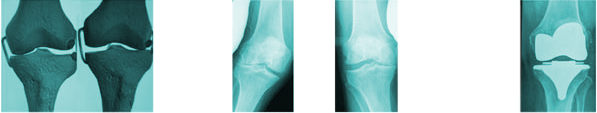

SCORE 6

90%

Medial Wear Bone on Bone Lateral Wear Bone on Bone